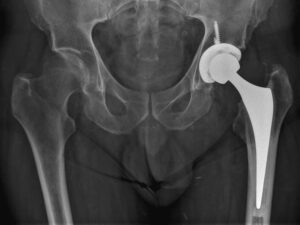

X-ray image of a hybrid THR where bone cement was used for femoral component fixation.

Dr Reddy uses uncemented implants in most patients younger than 80 years. These implants have a coating on their surface to allow bony integration with the patient’s own socket and femur allowing for a life-long bond. In elderly patients or patients with osteoporosis and poor bone quality, Dr Reddy uses bonecement to bond the femoral prosthesis to bone. This is called a hybrid THR.